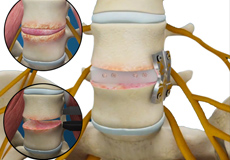

Lumbar Fusion

Spinal fusion, also called arthrodesis, is a surgical technique used to join two or more vertebrae (bones) within the spine. Lumbar fusion is the procedure of fusing the vertebrae in the lumbar portion of the spine (lower back). A piece of bone, taken from other parts of the body or donated from a bone bank is transplanted between the adjacent vertebrae. Screws, plates, or cages may be used with the bone graft to help hold the spine.